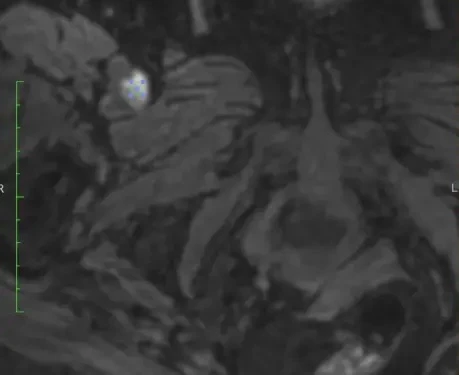

Клинический случай кавернозной мальформации, ассоциированной с венозной аномалией развития (ВАР). Следует напомнить, что ВАР часто сочетаются с каверномами, однако точные статистические данные не привожу, чтобы простимулировать самостоятельный поиск информации и закрепление знаний. Клиническая симптоматика у данного пациента отсутствует, что является типичным сценарием для подобных находок. Диагноз установлен случайно.